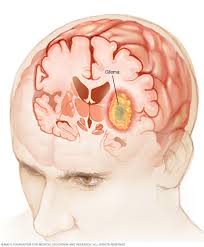

Metastatic tumors to the brain affect nearly one in four patients with cancer, or an estimated 150,000 people a year. New studies of epidemiological data from this country and abroad indicate that the rise is especially dramatic among the. This is ominous because as in smoking and cancer induction, a certain time span is required before cancer sets in the body and is recognised as such by medical and scientific bodies. Metastatic brain tumors (also called secondary brain tumors) are caused by cancer cells spreading (metastasizing) to the brain from a different part of the body.; Unlike cancers that start in other parts of the body, tumors that start in the brain or spinal cord rarely spread to distant organs. Since the early 1990s the possibility that exposure to radiofrequency (rf) radiation from wireless communications devices may be causing an increase in brain cancer has become a public concern, and. In adults, metastatic tumors to the brain are actually more common than primary brain tumors, and they are treated differently. The standard treatments for brain tumors include surgery, radiation and chemotherapy.

Brain and spinal cord tumors, like other tumors, are caused by changes in the dna inside cells. Treating brain tumors takes a team of. Metastatic tumors to the brain affect nearly one in four patients with cancer, or an estimated 150,000 people a year. Nearly 78,000 new cases of primary brain tumors are expected to be diagnosed this year. Unlike cancers that start in other parts of the body, tumors that start in the brain or spinal cord rarely spread to distant organs. It is also called a central nervous system tumor. (cnn)the incidence rate of aggressive malignant brain tumors in england has more than doubled in recent decades, and a new study questions what could be driving that rise. This information is about primary brain tumors. In general, brain tumors are more common among older people, but statistics even show an increase in brain tumors in kids. Metastatic brain tumors (also called secondary brain tumors) are caused by cancer cells spreading (metastasizing) to the brain from a different part of the body.; Addressing risk factors like smoking, obesity, sedentary lifestyle, and exposure to harmful environmental surroundings can go a long way toward improving your health and reducing your cancer risk. Soft tissue cancers, like those that develop. The standard treatments for brain tumors include surgery, radiation and chemotherapy.